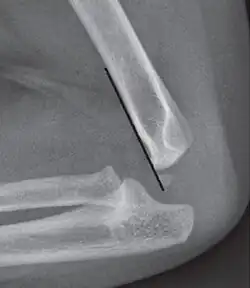

Anterior humeral line - It is a line drawn down along the front of the humerus on the lateral view and it should pass through the middle third of the capitulum of the humerus.[9] If it passes through the anterior third of the capitulum, it indicates the posterior displacement of distal fragment.[8]

Anterior humeral line (black line), with normal area passed on the capitulum of the humerus colored in green in a 4-year-old child.[9] -

The anterior humeral line is not reliable in children with sparse ossification of the capitulum, such as in this 6 months old child.[9]